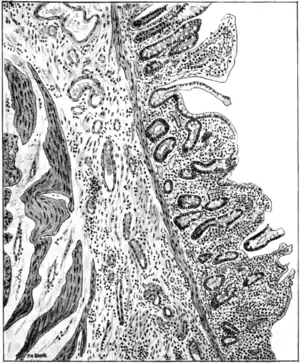

Morbid anatomy.— Post mortem the tissues in sprue are abnormally dry; fat is almost completely absent; the muscles and the thoracic and abdominal viscera are anæmic and wasted. With these exceptions and certain important changes in the alimentary tract, so far as known there are no special lesions which are invariably associated with this disease. According to Bertrand and Fontan, occasionally certain changes are present in the pancreas— namely, fatty or granular degeneration of the cells, with softening of isolated acini and slight inflammatory infiltration of the connective tissue. These, however, are not more constant than are certain other and similar changes occasionally found in the liver and kidneys. Sections of the tongue show desquamation of the epithelium, especially from the surface of the fungiform papillæ; an invasion of the epithelial cells by yeast fungi has been shown by Kohlbrügge to take place and is possibly a terminal infection.

Lesions of the alimentary tract.— The principal and characteristic lesions are found in the alimentary tract. The bowel is thinned to such an extent as to be almost diaphanous. The serous coat is generally healthy, the muscular coat atrophied. The submucosa in places has undergone hypertrophic fibrous changes; and the mucous membrane from mouth to anus, either in patches or universally, is superficially eroded and interstitially atrophied. The internal surface of the bowel is coated with a thick layer of dirty grey, tenacious mucus containing numerous yeast

cells and branching mycelium (Bahr), which conceals patches of congestion, of erosion, or even of ulceration, besides such evidences of similar antecedent disease as pigmented areas and thin-scarred, cicatricial patches. The villi and glands are eroded and in many places completely destroyed. Here and there minute spherical indurations, about the size of a pin's head and surrounded by a dark pigmented or congested areola, can be felt in the mucous membrane. On cutting into these, they are found to be minute cystlike dilatations of the follicles filled with a gummy, muco-purulent material. Sections of the diseased bowel (Fig. 83) show under the microscope corresponding changes, such as varying degrees of erosion or ulceration of the surface of the mucous membrane; degeneration of villi, glands, and; follicles; the small mucous cysts referred to; sometimes small abscesses; and, also, infiltration by leucocytes of the basement membrane and submucous layer; and, in the latter, fibro-cirrhotic changes. The mesenteric glands are generally large and pigmented, perhaps fibrotic. The erosion lesions are usually most marked towards the end of the ileum and in the colon; but they may be present in greater or lesser degree universally, or in patches throughout the entire alimentary tract from mouth to anus.